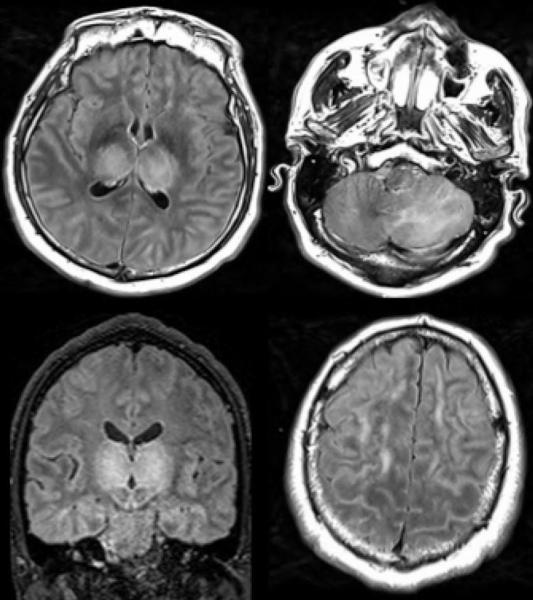

Among the 37 patients included, 28/37 (76%) were associated with one neuroimaging pattern, 7/37 (19%) with two patterns, and 2/37 (5%) showed three patterns. The most frequent MRI findings were: signal abnormalities located in the medial temporal lobe in 16/37 (43%) patients, non-confluent multifocal white matter hyperintense lesions on FLAIR and diffusion sequences, with variable enhancement, with associated hemorrhagic lesions in 11/37 patients (30%), and extensive and isolated white matter microhemorrhages in 9/37 patients (24%).